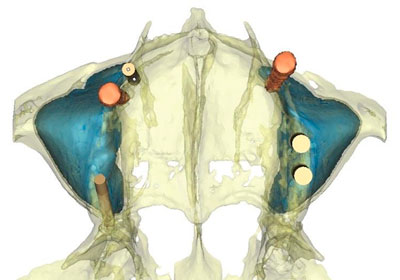

En el diagnostico en algunos casos es muy importante tomar una tomografía y realizar el estudio en 3D, para mayor seguridad del caso, en el estudio 3D podemos identificar por colores los espacios y estructuras anatómicas, así como también posicionar implantes dentales y conocer el número, tamaño y posición de los mismos.